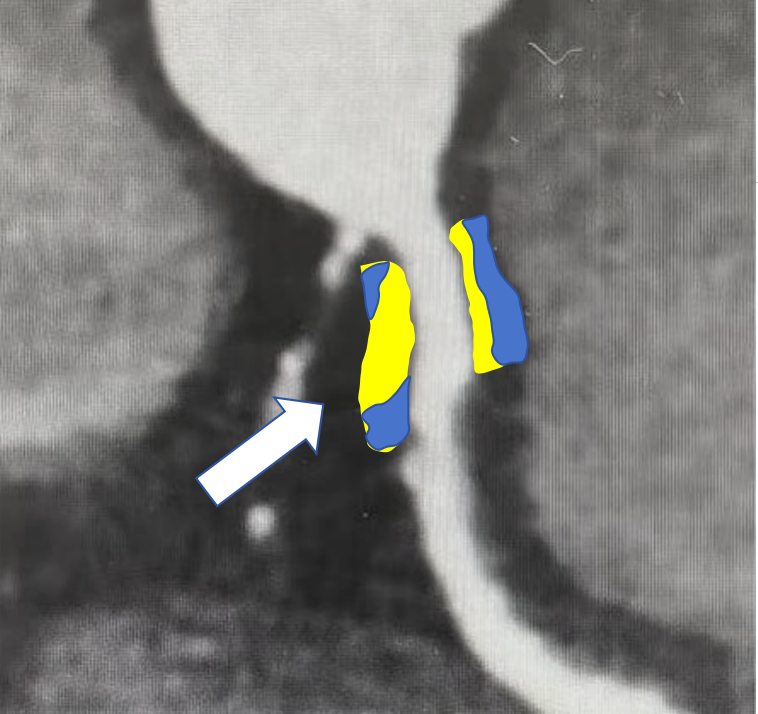

Methods: This study was a single-center, observational clinical cohort study. Patients who underwent coronary angiography and diagnosed with MINOCA in Fuwai Hospital from January 2015 to December 2019 and met the inclusion criteria were enrolled. We mainly explored the correlation between the FAI of right coronary artery and left circumflex and morbidity of AF. Kaplan-Meier analyses and Cox regression analyses were performed to evaluated cumulative NOAF hazard ratio during a 77.2-month follow-up. ROC analyses were also adapted in this study to detect the best cut-off value for FAI in predicting NOAF.

Results: A total of 592 MINOCA patients with coronary CT angiography were enrolled, including 40 (8.0%) with NOAF. CT was performed within two months before or after the onset of MI. Patients in higher median group of FAI had an apparently higher rate of NOAF (8.8% vs 4.7%; P<0.05) during the follow-up time. After adjusted for multiple clinically relevant variables, higher FAI was still associated with an increased risk of NOAF (HR=1.71; 95% CI: 1.23-2.39 P<0.001). Moreover, AMR had an AUC of 0.722 for NOAF prediction with the best cut-off value of -74.395 HU.

Conclusions:FAI score of main atrial coronary artery (RCA and LCX ), which may capture the risk of inflammation, is closely related to the atrial function. Higher FAI was a risk factor for NOAF in patients with MINOCA, which had high specificity and sensitivity for predicting NOAF in MINOCA patients. Assessment of FAI score derived from CCTA may increase predictability for NOAF in this special population.